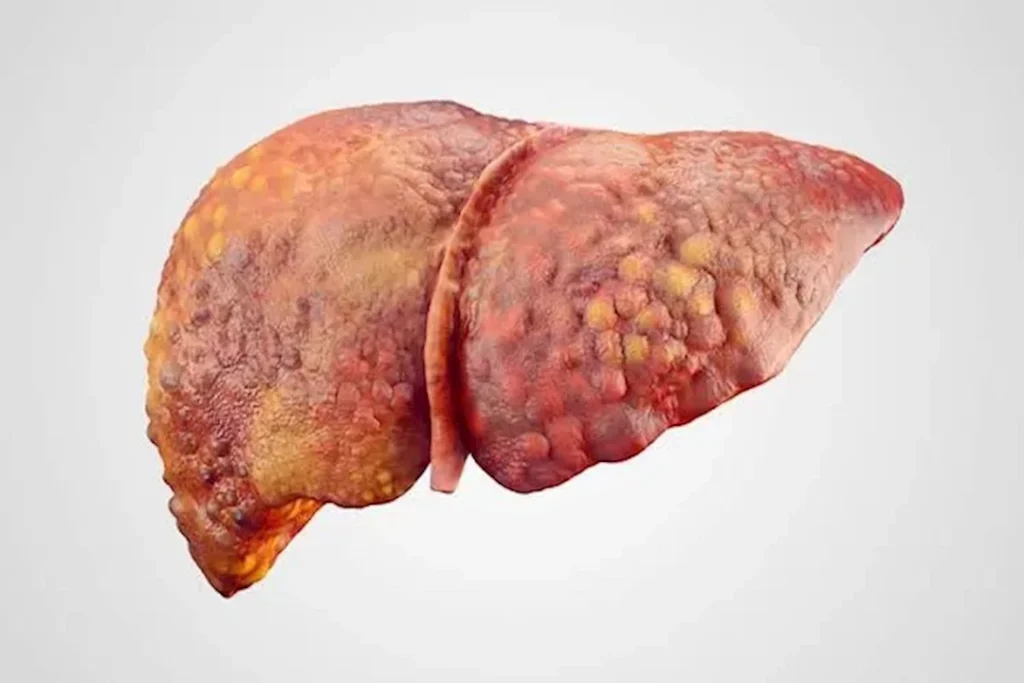

الكبد من أكبر وأهم أعضاء الجسم، حيث يؤدي وظائف ضرورية مثل التخلص من السموم، وتنظيم مستويات الدهون والسكريات، والمساعدة في عملية الهضم، ونظرًا لأهميته الكبيرة، فإن الحفاظ على صحته يعد أمرًا لا غنى عنه للوقاية من العديد من الأمراض.

وأكد “موافي” أن الكبد الدهني أصبح من أكثر المشكلات الصحية، نتيجة الإفراط في تناول الدهون وقد يسبب تليف الكبد، مشيرًا إلى أن اللحوم الحمراء تشكل عبئًا على الكبد.